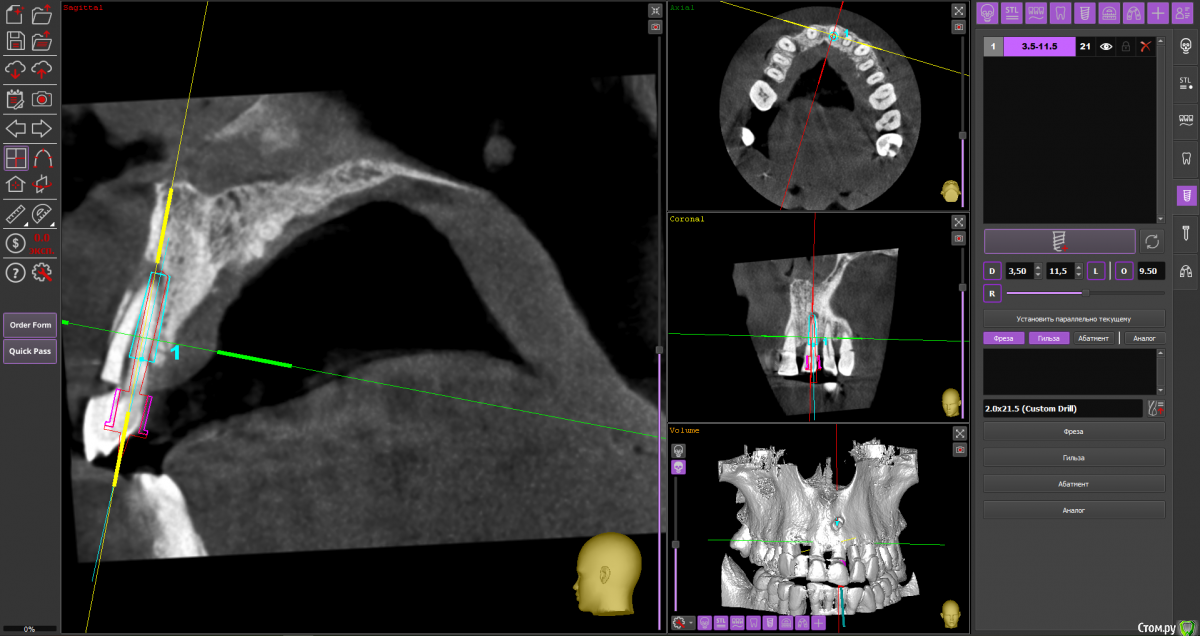

almaz7888 Опубликовано 28 января, 2021 Поделиться Опубликовано 28 января, 2021 Доброе утро коллеги! Планирую одномоментную имплантацию в область 2.1 зуба ( AnyRidge 3.5*11.5). В области апекса костный дефект. Думаю заполнить ксенографтом и перекрыть резорбируемой мембраной 1.5*2.0. Думал насчет спейсера Стоит ли такой имплант сразу нагрузить? или же лучше сделать адгезивный мост. Ссылка на комментарий

alboard Опубликовано 28 января, 2021 Поделиться Опубликовано 28 января, 2021 В том положении, которое на кт, сомневаюсь, что получите торк и сможете нагрузить... Взять подлиннее, поставить небнее и заглубить еще 4 Ссылка на комментарий

Irouil Опубликовано 28 января, 2021 Поделиться Опубликовано 28 января, 2021 Винт длиннее, выход в резцовый, стт, временная коронка 1 Ссылка на комментарий

almaz7888 Опубликовано 28 января, 2021 Автор Поделиться Опубликовано 28 января, 2021 Спасибо, тогда возьму 3.5*15. А резцовый нерв коагулирую и заполняю канал графтом или же можно без прижигания обойтись? Ссылка на комментарий

Irouil Опубликовано 28 января, 2021 Поделиться Опубликовано 28 января, 2021 Резцовый - это край, а не канал) Дальше либо цемент через индивидуальный абатмент, либо угловой абатмент и шаровидная отвёртка под винтовую 2 Ссылка на комментарий